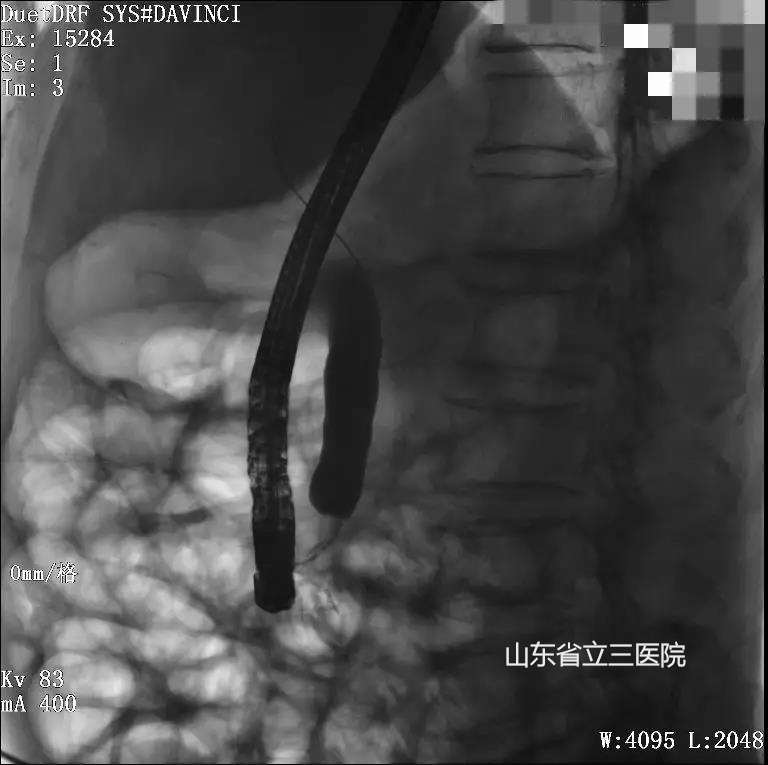

術(shù)前造影顯示患者腫瘤已致膽管阻塞